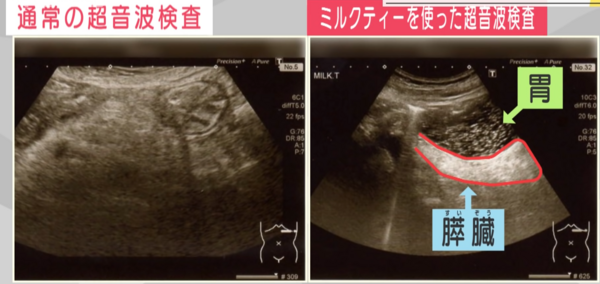

▲胰臟的畫面。左邊是正常的超音波檢查,右邊是喝「午後紅茶奶茶」後的畫面。(圖/翻攝日本朝日電視台)

根據日本朝日電視台報導,胰臟位於胃的後方,通常只看得到一半,即使罹患胰臟癌也非常難以發現,在醫界被稱為「黑暗器官」。不過日本醫界日前找到檢驗胰臟癌的小撇步,就是在照超音波前,讓患者先喝一罐日本知名飲料品牌「午後紅茶」的奶茶,約有7成機率能及早發現胰臟癌病變。

片山醫生表示,如果胃中有奶茶,約可看到9成左右的胰臟,對早期發現胰臟癌非常有幫助。至於為什麼一定要奶茶,不能是檸檬紅茶或其他飲料?片山則補充說明道,因為檸檬會導致胃中產生胃酸,而碳酸飲料則會產生很多小氣泡,導致更看不清楚胰臟;但奶茶的濁度卻正好有助於超音波檢驗。